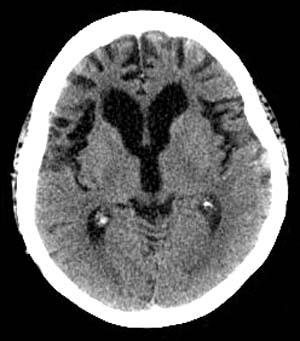

Radiographically Pick's disease, a variant of Frontotemporal dementia, appears as prominent atrophy of the temporal and/or frontal lobes on CT. Sulcal prominence, widening of the Sylvian fissure with atrophy of the insula, inferior frontal and superior temporal lobes, as well as enlargement of the frontal or temporal horns of the lateral ventricles is most evident on MRI. In addition, MR volumetric analysis may show subtle involvement of the orbitofrontal cortex.

![]() ![]() The images above are axial Head CT scans. |